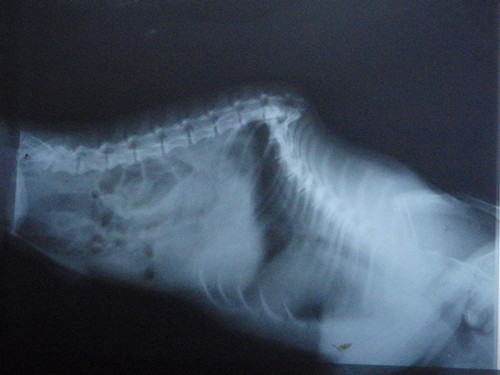

这是一例车祸导致腰椎折断的病例,双侧后肢瘫痪,无知觉,但主人不离不弃,一直照顾,并进行中医疗法进行针灸,后肢已经稍有感觉。

犬腰椎折断